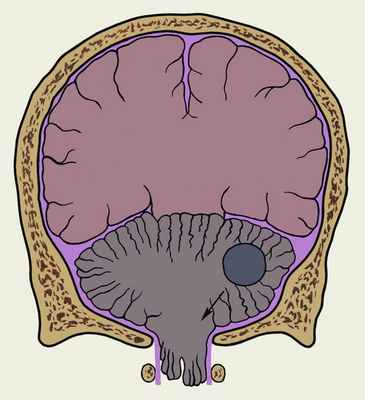

При опухолях височной доли мозга, реже опухолях лобной или затылочной долей может наблюдаться оттеснение головного мозга спереди назад и медиально. При этом медиальные участки полушарий вклиниваются в отверстие намета мозжечка, сдавливая проходящий через это отверстие ствол мозга (рис. 2). Такое тенториальное вклинение в зависимости от степени и симметричности сдавления ствола вначале может клинически проявиться синдромом внутричерепной гипертензии и симптомами одностороннего поражения ствола головного мозга. Однако вскоре стволовые симптомы становятся двусторонними, усиливаются головная боль и рвота, углубляется нарушение сознания. Стволовой синдром тенториального вклинения характеризуется парезом взора вверх, отсутствием зрачкового светового рефлекса, слабостью конвергенции, наличием двусторонних патологических пирамидных рефлексов и др. Сдавление на основании головного мозга глазодвигательного нерва обусловливает птоз, косоглазие, расширение зрачка на стороне поражения. Прогрессирование явлений тенториального вклинения ведет к развитию параличей, децеребрационной ригидности (Децеребрационная ригидность), комы.

Рис. 2. Схематическое изображение фронтального разреза головы при синдроме тенториального вклинения, обусловленном опухолью височной доли: стрелка, идущая от опухоли, показывает направление вклинения вещества полушарий большого мозга.